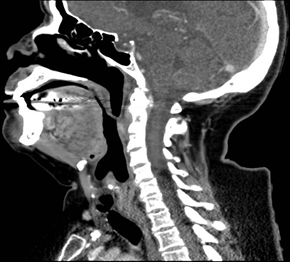

A 75-year-old female patient with no known pathological history, no surgical history. He came to our consultation referred by the pulmonology service due to progressive inspiratory dyspnea, laryngeal stridor with effort and rest, without dysphonia of 2 years of evolution, previously ruling out pathologies by pulmonology and cardiology. On physical examination, a nasofibrolaryngoscopy was performed, visualizing decreased subglottic lumen with good mobility of the vocal cords, normal mucosa and no laryngeal lesion. A stroboscopy is performed, visualizing subglottic stenosis of more than 60% of the glottic lumen (Figure 1), confirming with Computed Axial Tomography (Figure 2), reporting an infraglottic membrane that conditions slight reduction of the airway with the presence of a false lumen of 10 x 3 mm on the left side and 3 x 2 mm on the right side of the airway. In addition, complementary analytical studies to rule out inflammatory diseases as a possible cause, these being negative. He was scheduled to perform tracheostomy plus laryngeal microsurgery with CO2 laser resection and topical Mitomycin C. Pathological anatomy sample is sent reporting Fibro-leukocyte material, Subglottic Lesion. Currently exhaustive control by outpatient, patient is without dyspnea, without stridor and decannulated with more than 1 year post-surgery.